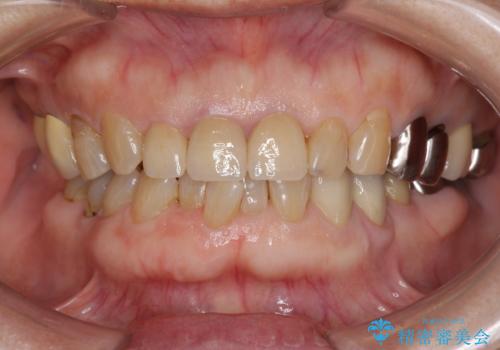

前歯の審美改善

- 孫娘の結婚式に合わせて前歯を綺麗にして写真映りをよくしたいと来院されました。

結婚式に合わせて根管治療からのやりかえを短期集中治療で計4回で終える計画を立てます。